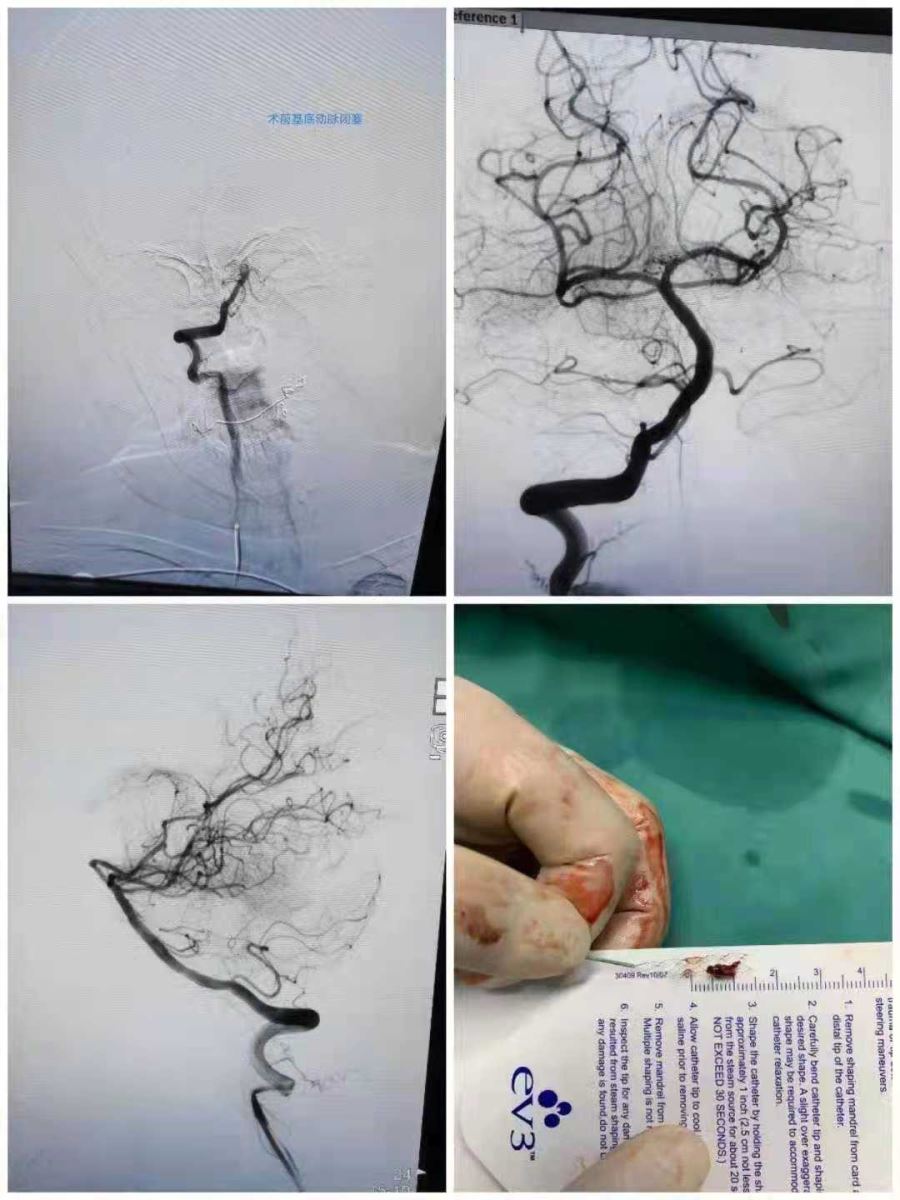

近日,我院神经内四科辛志强医生、包瑛医生成功为一位83岁高龄老人实施支架取栓术,使患者转危为安,获得了良好的预后机会。

8月7日,老人因突发意识不清到我院就诊,卒中中心值班医生刘书函接诊后迅速判断病情,考虑老人病症且既往有房颤病史,高度怀疑脑梗塞,临床分型考虑为后循环梗死,属临床急危重症,刘医生马上为患者开通绿色通道,二线介入医生辛志强、包瑛评估后认为介入取栓治疗是最优的治疗方案,但是由于事发突然,老人年纪较大,家属犹豫不决,在辛志强医生细心讲解下,最终患者家属放下顾虑,同意手术。辛志强医生为术者,包瑛医生为助手。该手术属于难度较大的四级手术,且患者为高龄老人,使手术难度再次升级,稍有不慎就会给患者造成不可挽回的后果。辛医生凭借过人的魄力和丰富的手术经验,顺利将血栓取出,术后老人意识逐渐转清,并在护理团队的精心照料下,5天后日常活动基本不受限,逐步恢复正常生活。老人和家属感动之余,特意为我院神经内四科团队送来了一面写有“医德高尚、医术精湛”的锦旗。金杯银杯不如百姓的口碑,患者的认可是对我院最大的鼓励。

目前,我院卒中中心针对急性脑梗死介入取栓技术处于通辽地区领先水平,此次手术的成功,充分彰显了我院卒中中心应对各种急危重症以及复杂急性脑血管病的救治能力,是我院在党史学习教育开展以来的又一实际成效。今后,我院将持续地把“学党史 悟思想 办实事 开新局”推向深入,从党史学习教育中不断汲取前行的力量,在医疗服务中切实为更多患者群众解难题、办实事,以昂扬姿态奋力建设一流医院,全力为人民的健康保驾护航。